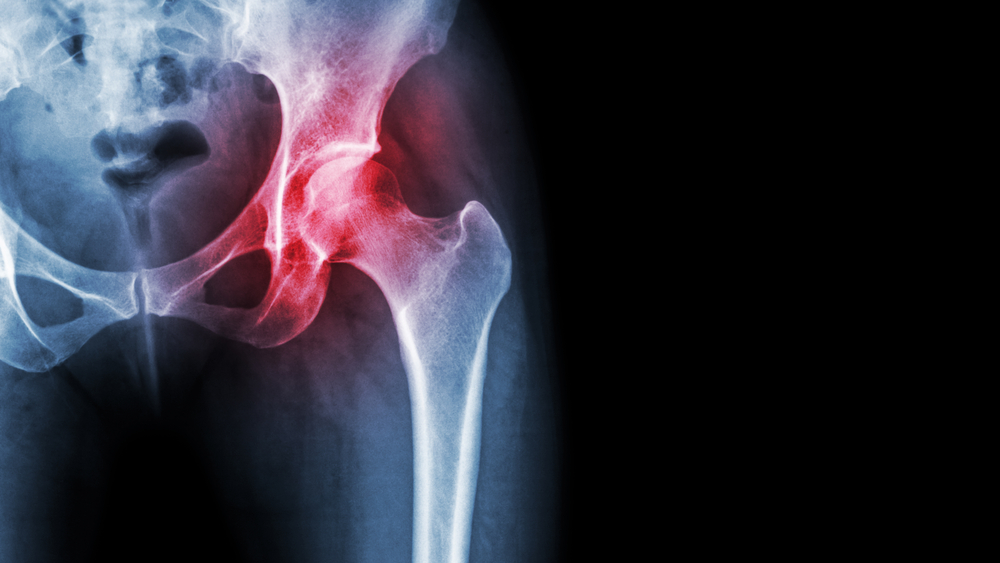

Τα γόνατα και τα ισχία (γοφοί) είναι οι μεγαλύτερες αρθρώσεις του ανθρώπινου σώματος.

Υποστηρίζουν όλο το σωματικό βάρος και λειτουργούν σε στενό συντονισμό, έτσι ώστε να μπορούμε να βαδίζουμε, να τρέχουμε, να αθλούμαστε και να σηκώνουμε βάρος.

Με την πάροδο του χρόνου, πολλοί αρχίζουν να αισθάνονται πόνο λόγω της οστεοαρθρίτιδας, μιας διαδικασίας φθοράς των αρθρώσεων από την υπέρχρηση και καταπόνησή τους.

1) Ποιο είναι πιο εύκολο να εκτελεστεί, αντικατάσταση ισχίου ή γόνατος;

Στην αρθροπλαστική του ισχίου ένας έμπειρος χειρουργός χρειάζεται μεγάλη γνώση της εμβιομηχανικής για την τοποθέτηση των εμφυτευμάτων αλλά η επέμβαση χαρακτηρίζεται πιο ήπια με μικρότερη βαρύτητα στα χέρια πάντα ενός έμπειρου χειρουργού.

Η αντικατάσταση του ισχίου είναι μια πολύ λιγότερο επώδυνη επέμβαση.

Οι ασθενείς χρησιμοποιούν πατερίτσες για λίγο και στη συνέχεια αισθάνονται τα ισχία τους  φυσιολογικά.

Το ισχίο είναι πιο απλή άρθρωση ενώ το γόνατο πρέπει να εξισορροπήσει  φορτία πιο μακριά από το κέντρο βάρους αλλά και να κάνει πιο πολύπλοκες κινήσεις.